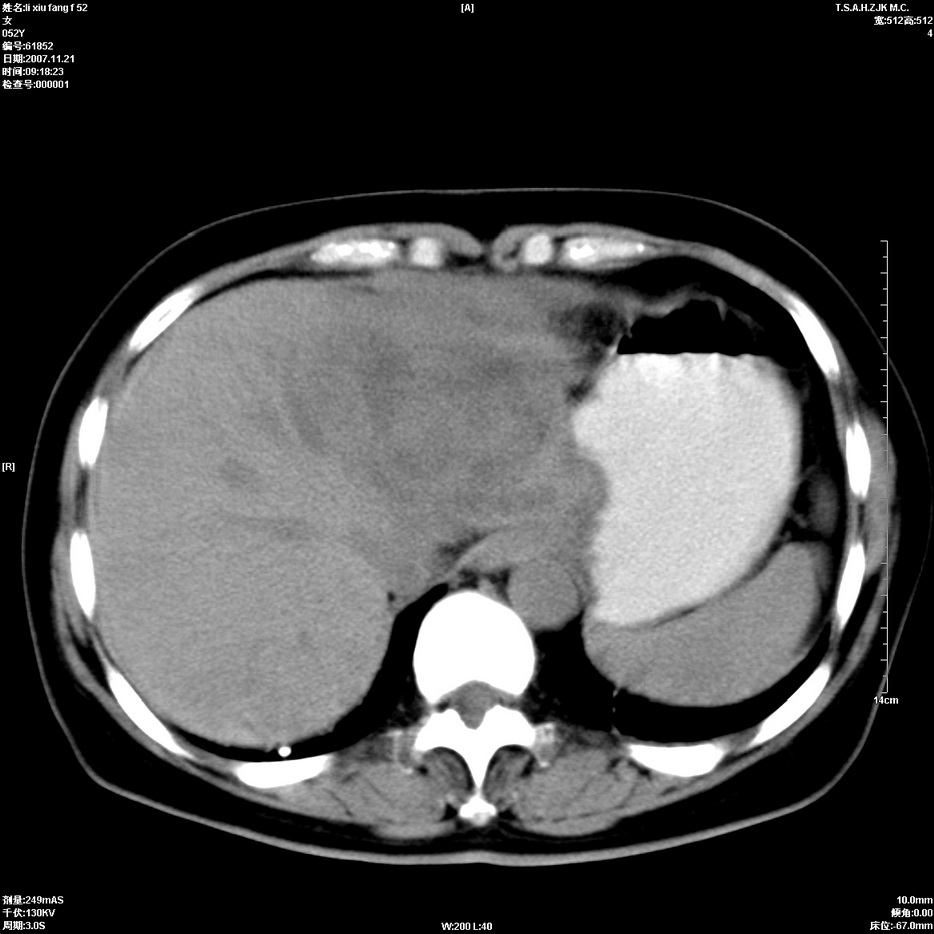

标题: CT12858:女,52岁,胎甲球蛋白861肝左叶占位,肝癌。下腔静 [打印本页]

标题: CT12858:女,52岁,胎甲球蛋白861肝左叶占位,肝癌。下腔静

肝左叶巨大低密度灶肿块,增强符合快进快出表现,有动静脉交通支;静脉期,下腔静脉内有充盈缺损,afp明显升高,支持肝癌并下腔静脉癌栓形成。

以下是引用拾荒者在2008-4-15 22:57:00的发言:[br]肝左叶巨大低密度灶肿块,增强符合快进快出表现,有动静脉交通支;静脉期,下腔静脉内有充盈缺损,afp明显升高,支持肝癌并下腔静脉癌栓形成。